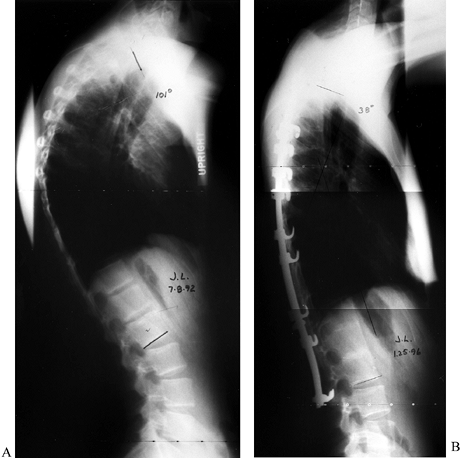

![]() |

|

Figure 161.7. A: An 18-year-old man with 101° thoracic kyphosis from Scheuermann’s disease. B:

Four years after staged anterior interbody fusion and posterior fusion and segmental instrumentation. The kyphosis is corrected to 38°. |